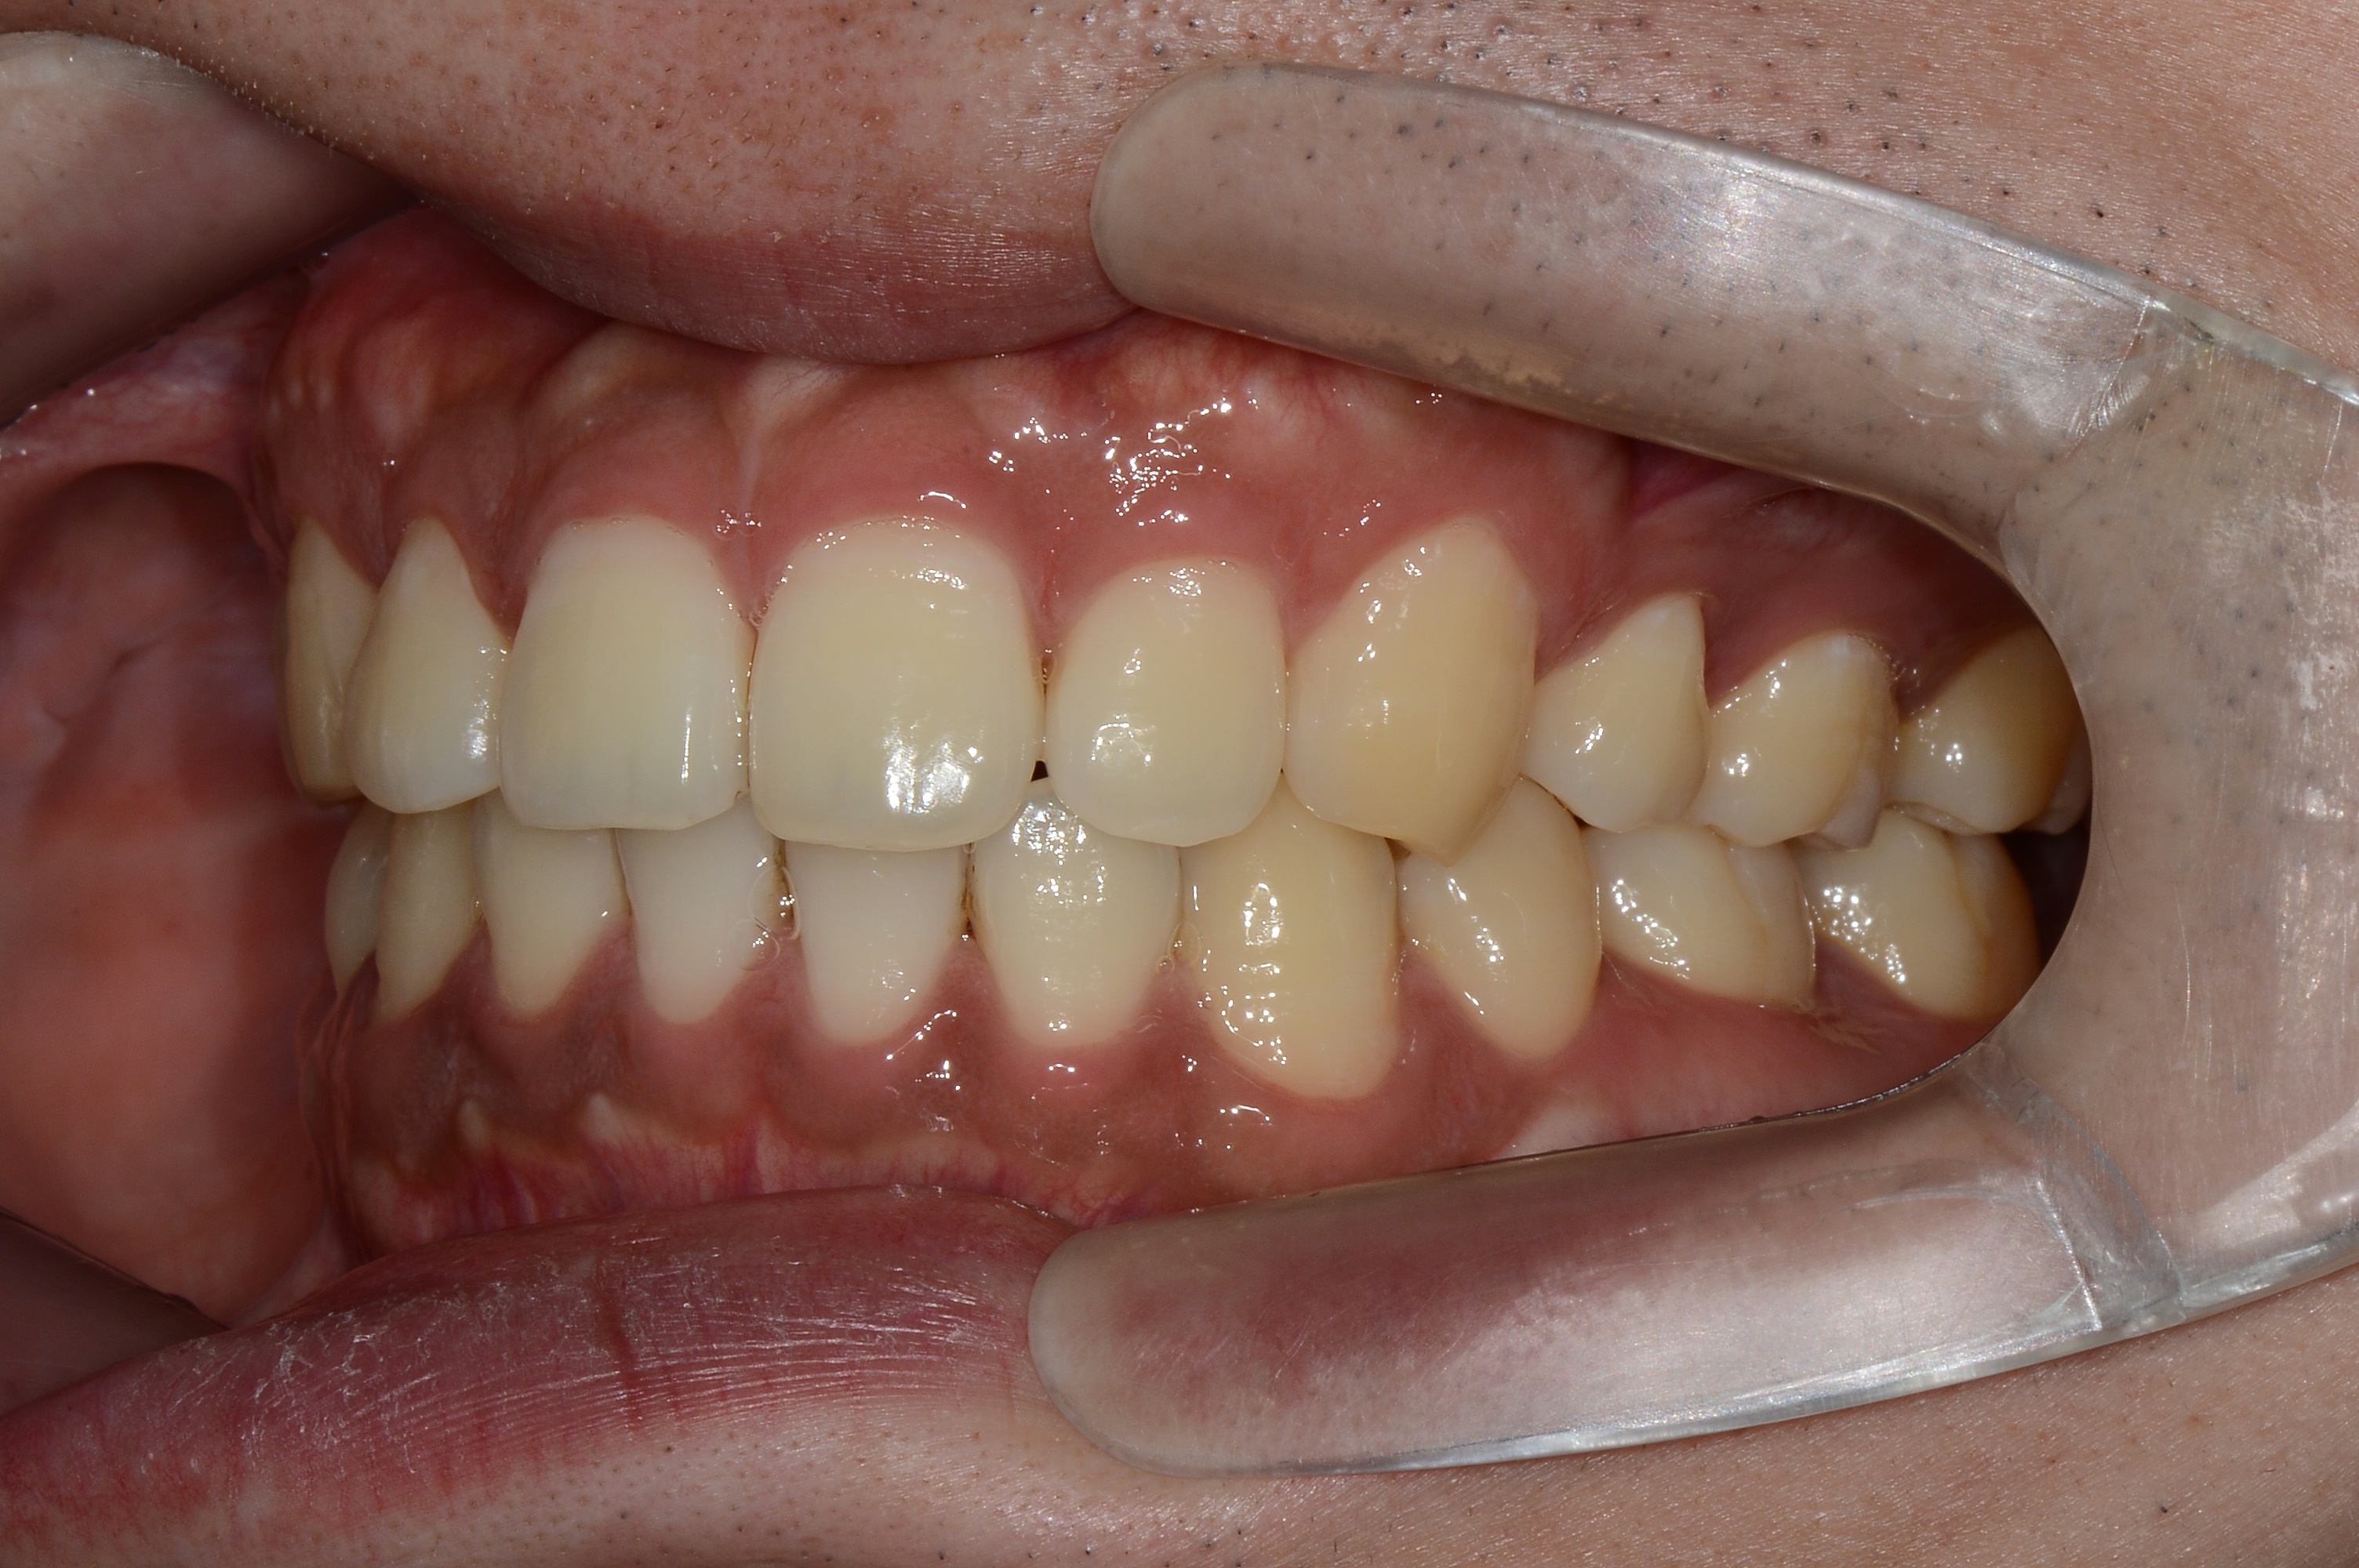

[돌출입] 돌출입